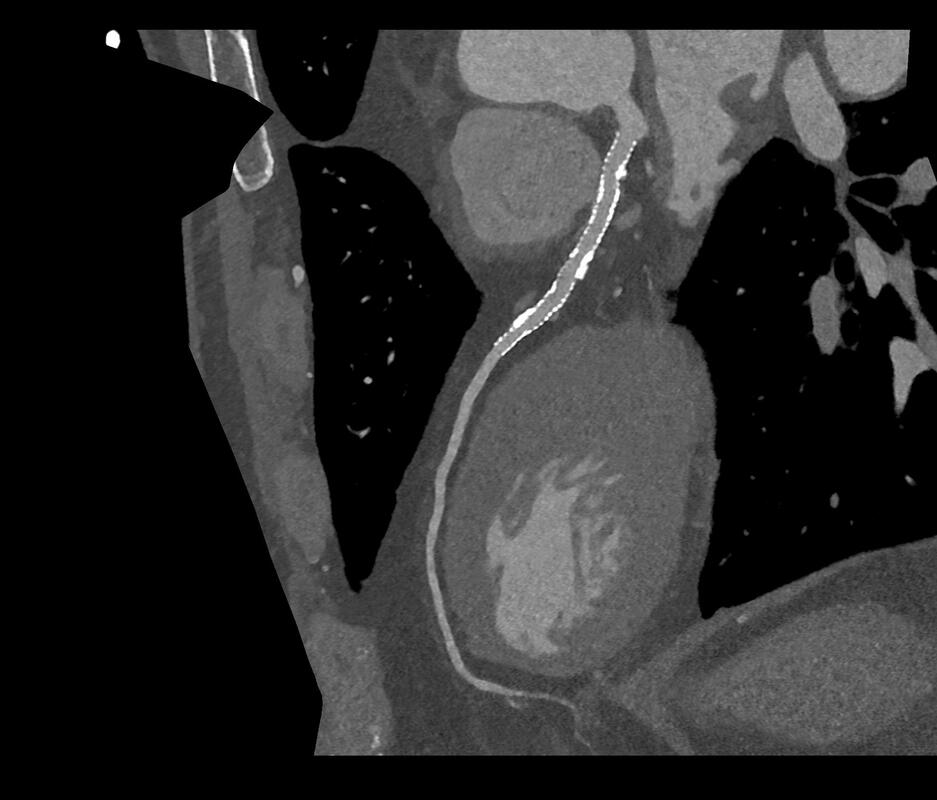

In-stent evaluation becomes feasible in clinical routine, thanks to the unique combination of resolution, spectral capabilities, and high temporal resolution of the NAEOTOM Alpha CT scanner. Image courtesy of Center Cardio-Thoracique de Monaco, Monaco via Siemens Healthineers.

Further to this, the scanner’s revolutionary detector allows our specialists to see inside coronary stents as small as 2mm in diameter (well below the limits of resolution for traditional CT scanners), as well as reducing artefact from metal objects like pacemakers and the larger stents found around TAVI valves.

With its precise imaging, our specialists can better characterise the composition and severity of coronary artery stenosis caused by atheromatous plaque, reducing the need for invasive coronary catheter examinations or further investigation. This provides improved accuracy for characterisation of the disease present in coronary arteries, to help our consultants develop the best-informed treatment strategy for patients.

In terms of image quality, the NAEOTOM Alpha provides slices as small as 0.2mm (compared to 0.5mm for traditional CT scanners), even for patients with a high BMI. This resolution is the highest available for any CT scanner currently, which greatly increases diagnostic confidence. It is this very high resolution that enables our specialists to assess for blockages even within small coronary stents, a task that is often not possible via traditional CT technology.